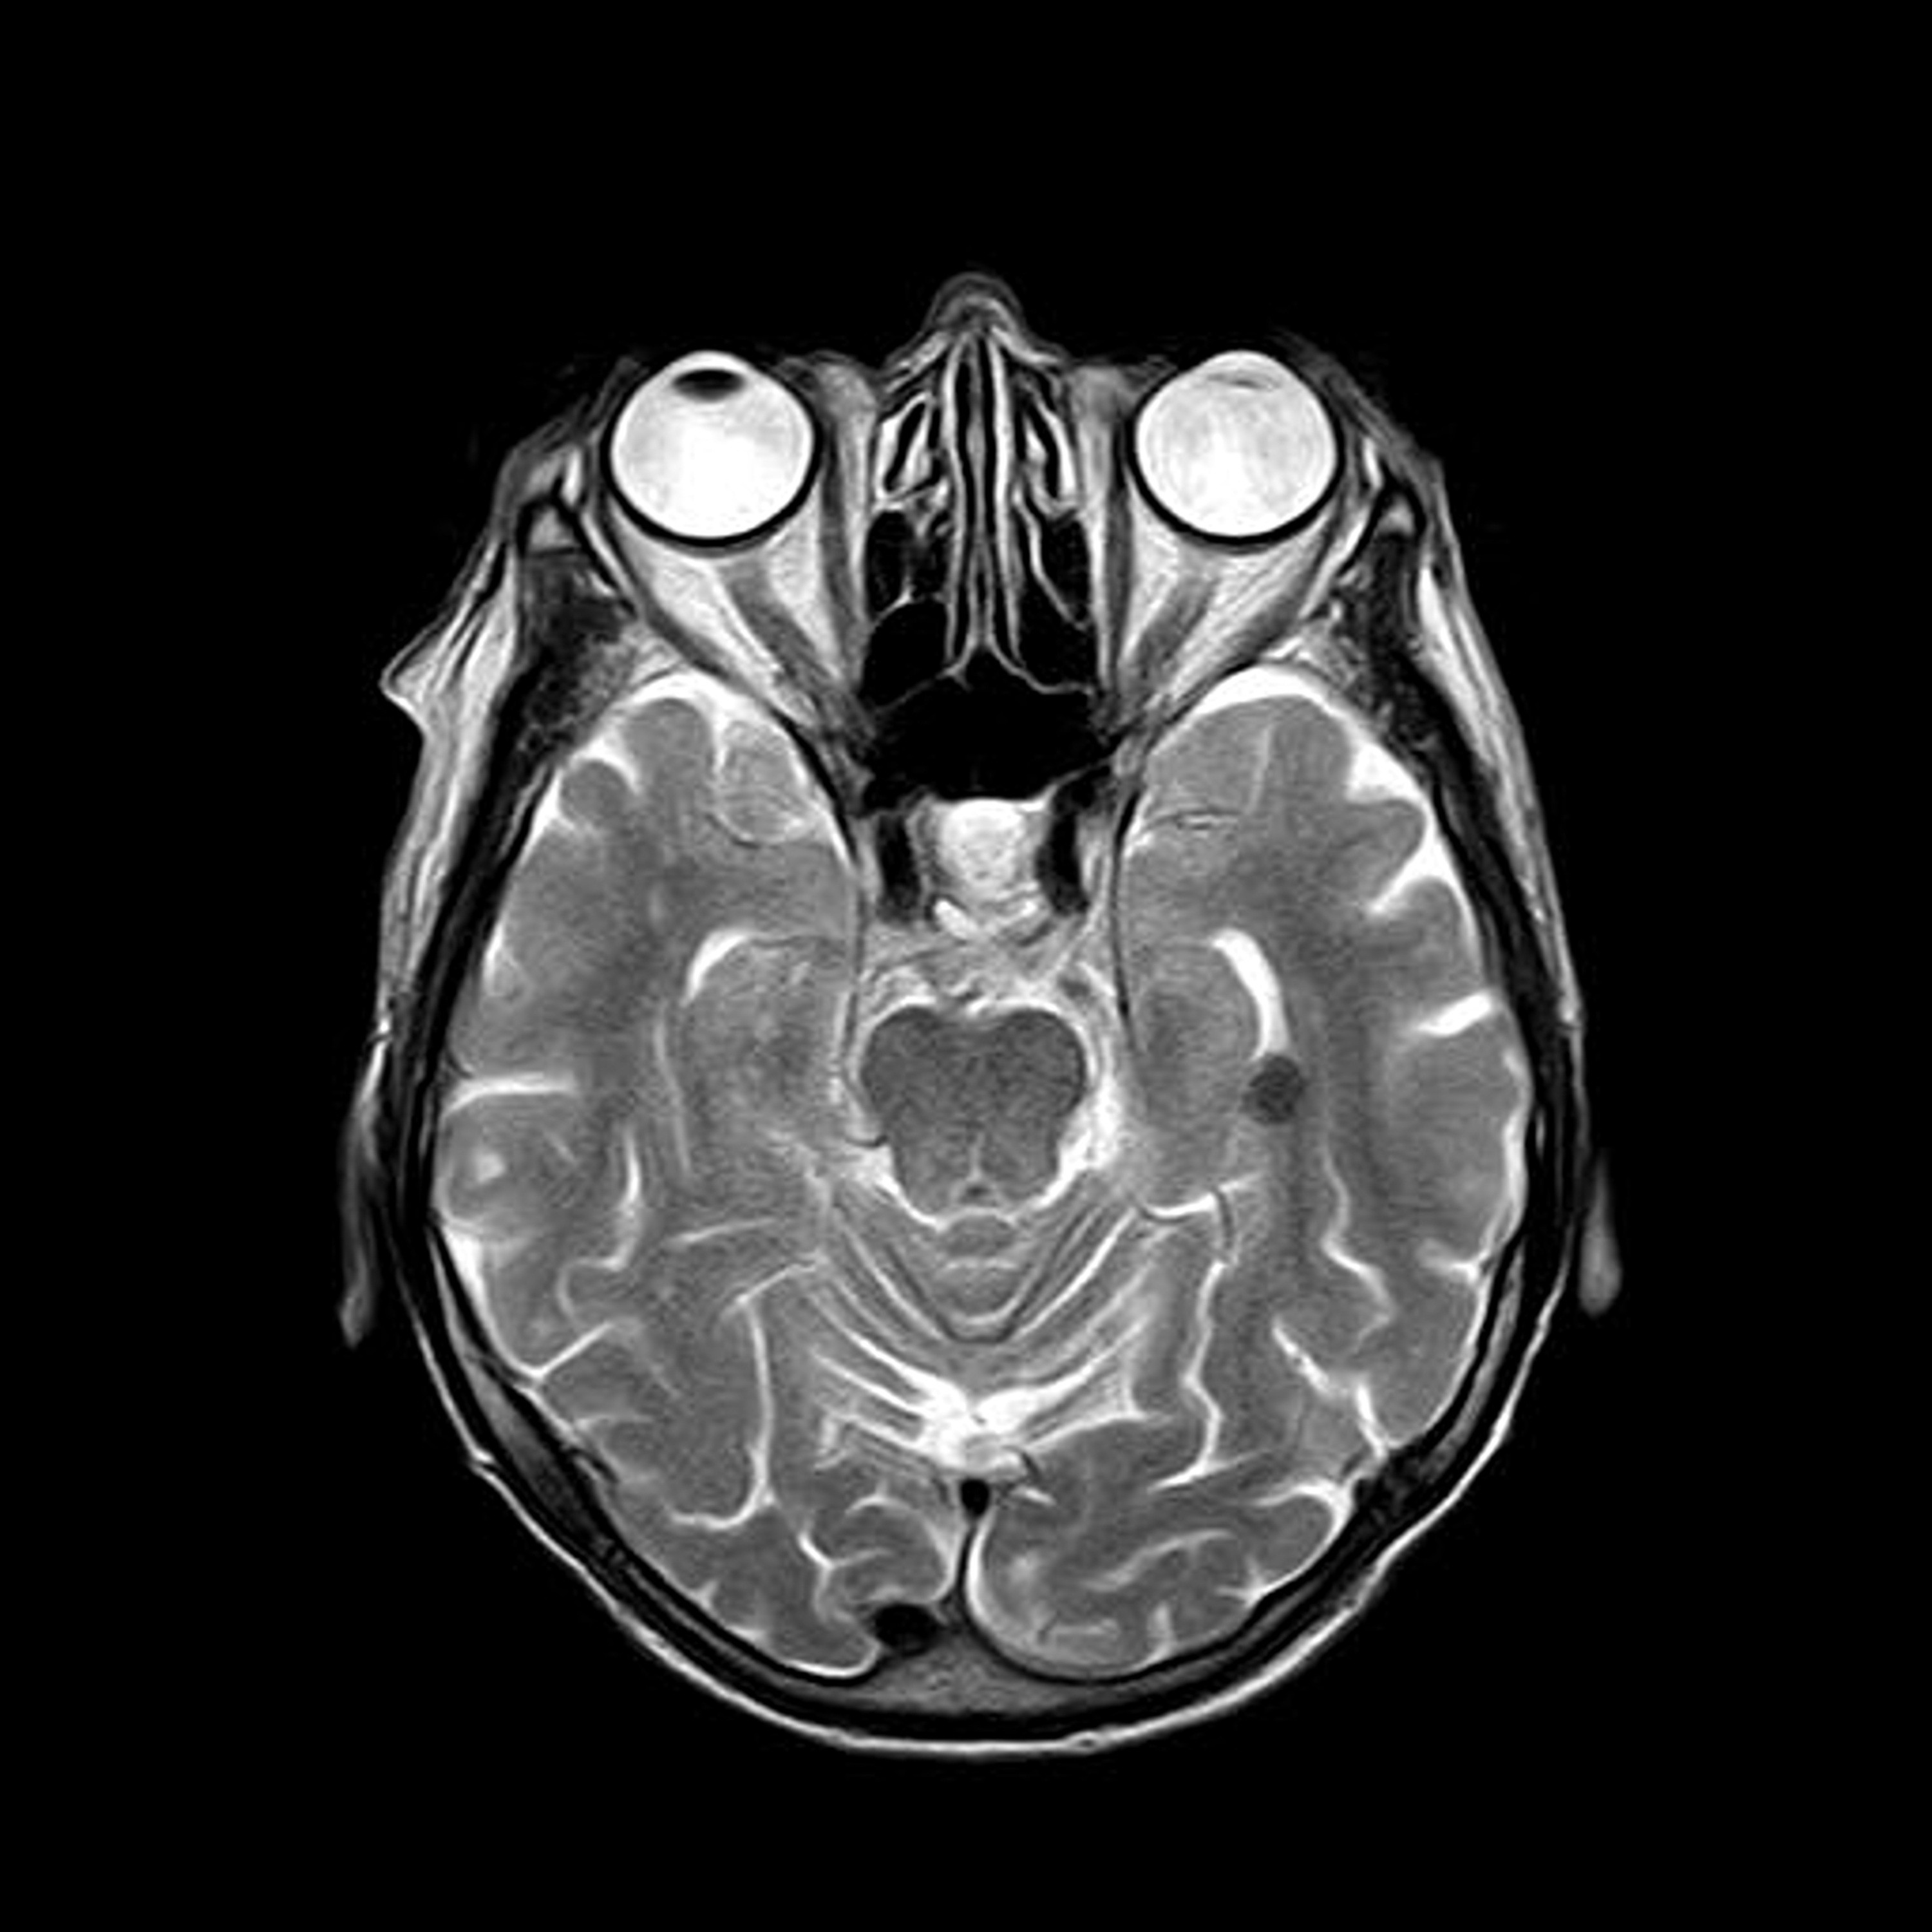

Understanding the brain requires more than theory.

It requires tools.

But their brain does. Emotions happen before language. Sensation happens before logic. The body reacts before the mind explains. So we observe the brain directly.